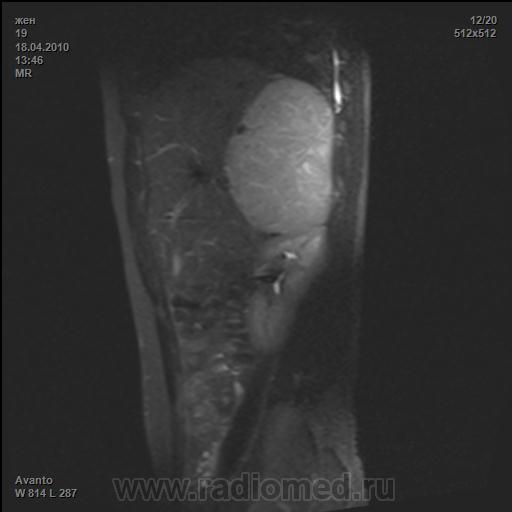

Больная 19 лет,обратилась с диагнозом адреногенитальный синдром,тестостерон 425!!!,менструации отсутствуют,оволосенение по мужскому типу .ВыполненоМРТ.

На серии МР-томограмм брюшной полости из правого надпочечника исходит образование, размерами 9.3х8.4х11.6 см, с ровными четкими контурами. Печень компремирована, оттеснена кпереди и кверху, без признаков инвазии. Образование дает неоднородный МР-сигнал, преимущественно гиперинтенсивный на Т1ВИ и Т2ВИ, и на ИП с жироподавлением. Неоднородность обусловлена наличием стромального и сосудистого компонента. Образование имеет четко выраженную капсулу и прилежит к верхнему полюсу правой почки без признаков инвазии.

ЗАКЛЮЧЕНИЕ: МР-картина образования надпочечника (наиболее вероятно макроаденома).

Рекомендовано: Для верификации злокачественности МРТ с динамическим контрастированием. Консультация хирурга-онколога.